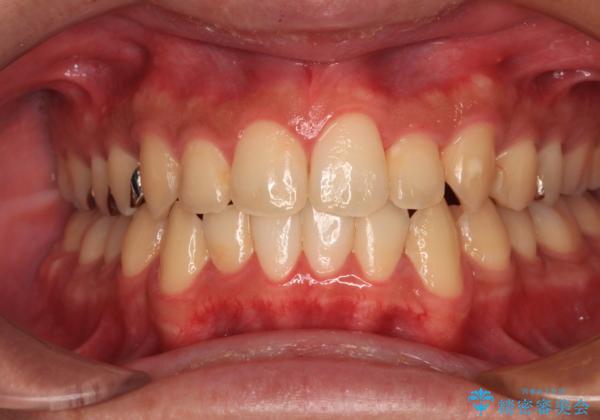

前歯のクロスバイト インビザラインによる矯正治療

- 上下のクロスバイトと前歯のデコボコを気にして来院された患者様です。

インビザラインを用い、IPR(歯と歯の間を削る)と歯列全体を拡大させることで、歯並びを整えていくこととしました。

インビザライン特有の、治療後半に奥歯が咬み合わないという事象が長引きました。

咬み合わないときの対処方法は色々とありますが、ゴムかけなどを活用して噛めるようにしました。